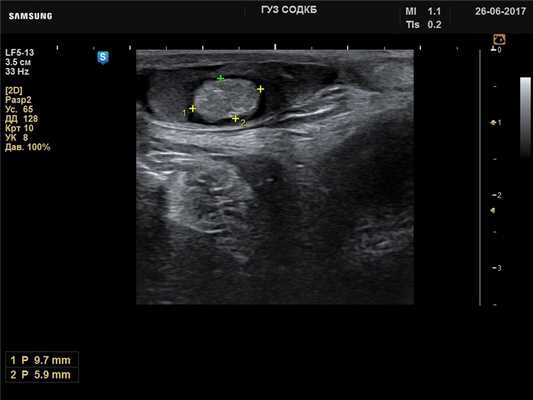

Яичко - дермоидная киста, B-режим

[EN] Эхограмма №732: Дермоидная киста яичка у ребенка 7 лет. Левое яичко. Линейный датчик 5-13 МГц, B-режим (продольно).

Автор: Суханов С.А., Саратов.

Изображение получено с помощью УЗ сканера H60 (снят с производства).